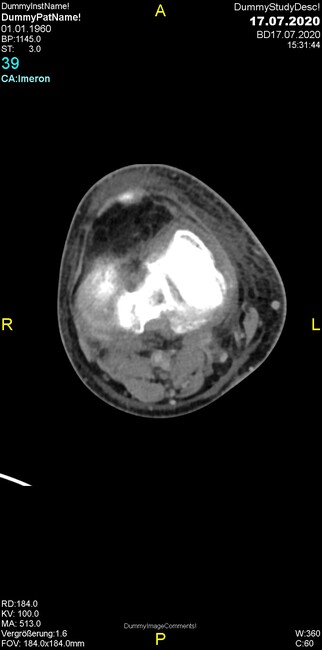

Um welche Modalitäten handelt es sich?

- Röntgen p.a. und lateral, CT coronar Knochenfenster, CT axial Weichgewebsfenster

- Röntgen p.a. und oblique, CT coronar Knochenfenster, CT axial Weichgewebsfenster

- Röntgen p.a. und lateral, CT sagittal Weichgewebsfenster, CT coronar Knochenfenster

- Röntgen p.a. und oblique, CT sagittal Knochenfenster, CT coronar Weichgewebsfenster

- Röntgen p.a. und lateral, CT coronar Weichgewebsfenster, MR axial

Was trifft auf den Befund zu?

- Der Befund beschränkt sich auf den Knochen.

- Es besteht hochakuter Handlungsbedarf.

- Der Befund ist tendenziell benigne.

- Der Befund ist tendenziell maligne.

- Der Befund weist einen Zusammenhang zum Patientenalter auf.

Was kommt differentialdiagnostisch in Frage?

- Kompartmentsyndrom

- Osteomyelitis mit Weichgewebsanteil

- Metastase mit pathologischer Fraktur

- Rheumatoide Athritis

- Posttraumatische Verletzung